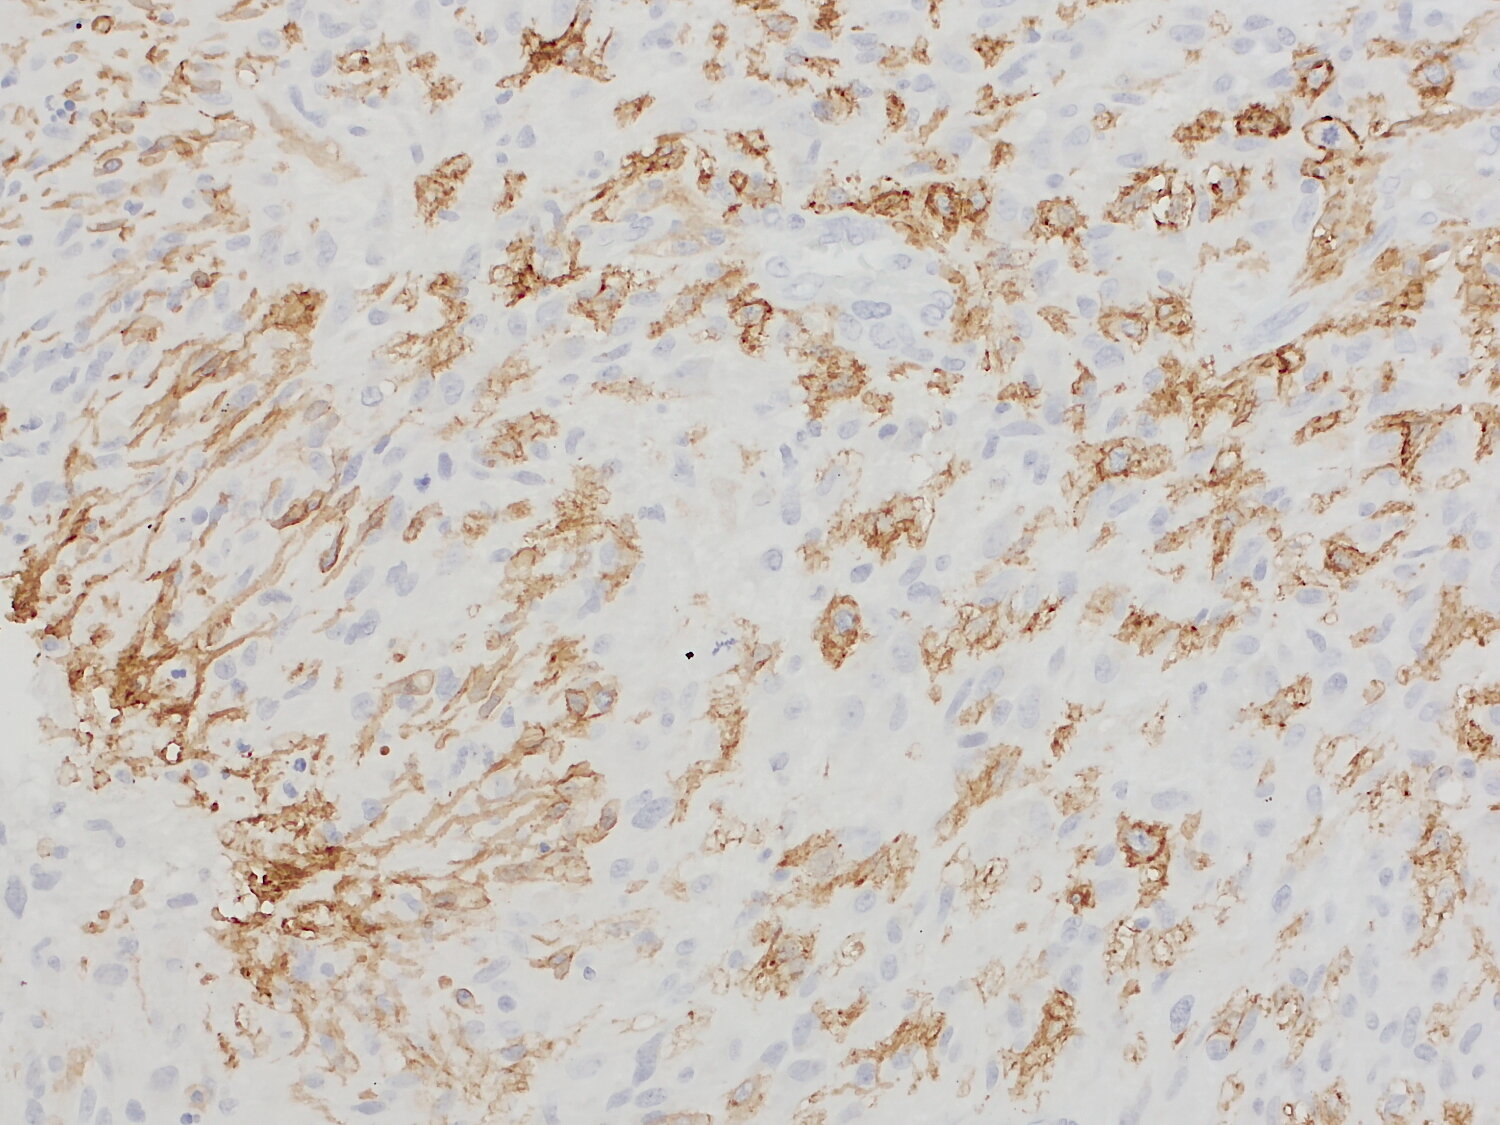

IP: not tested yet ICC: not tested yet IHC: not tested yet IHC-P: 1 : 1000 gallery |

Microglia are resident myeloid cells of the central nervous system (CNS). They are ontogenetically and functionally distinct from monocyte-derived macrophages that infiltrate the CNS under pathological conditions. Transmembrane protein 119 (TMEM119) is a single-pass type I membrane protein that has been identified as a useful, highly selective microglia marker protein.